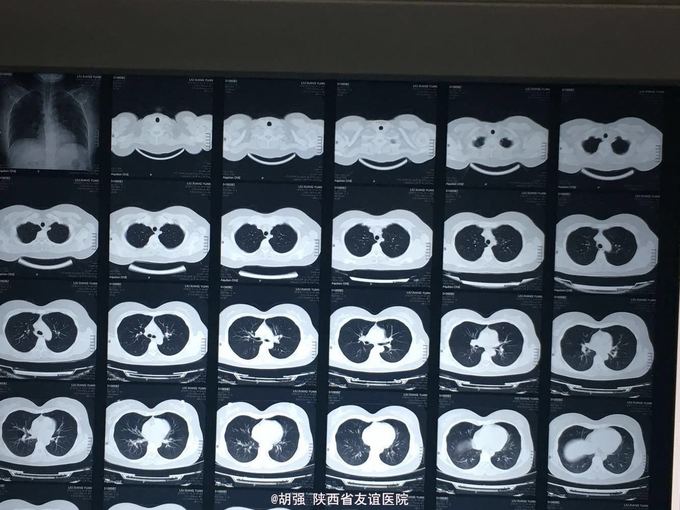

32岁女性患者,咳嗽、咳痰2周余 患者于两周前不明诱因出现咳嗽、咳痰,无胸痛咯血,无胸闷气短,无发热、寒战,自己服用头孢克肟1.0 2次/日及复方甘草合剂10ml3次/日治疗1周,效果不佳,遂来我院。 既往体检。

查体:两肺呼吸音粗糙,未闻及干湿性啰音及胸膜摩擦音。余查体无明显异常。 入院后查胸部CT无明显异常。血常规、肝肾功、血沉、结核抗体、心电图大致正常。T-sport试验及PPD试验 阴性。支气管镜检查:右肺中叶可见大量脓痰,吸痰送检。痰培养回报:肺炎链球菌。